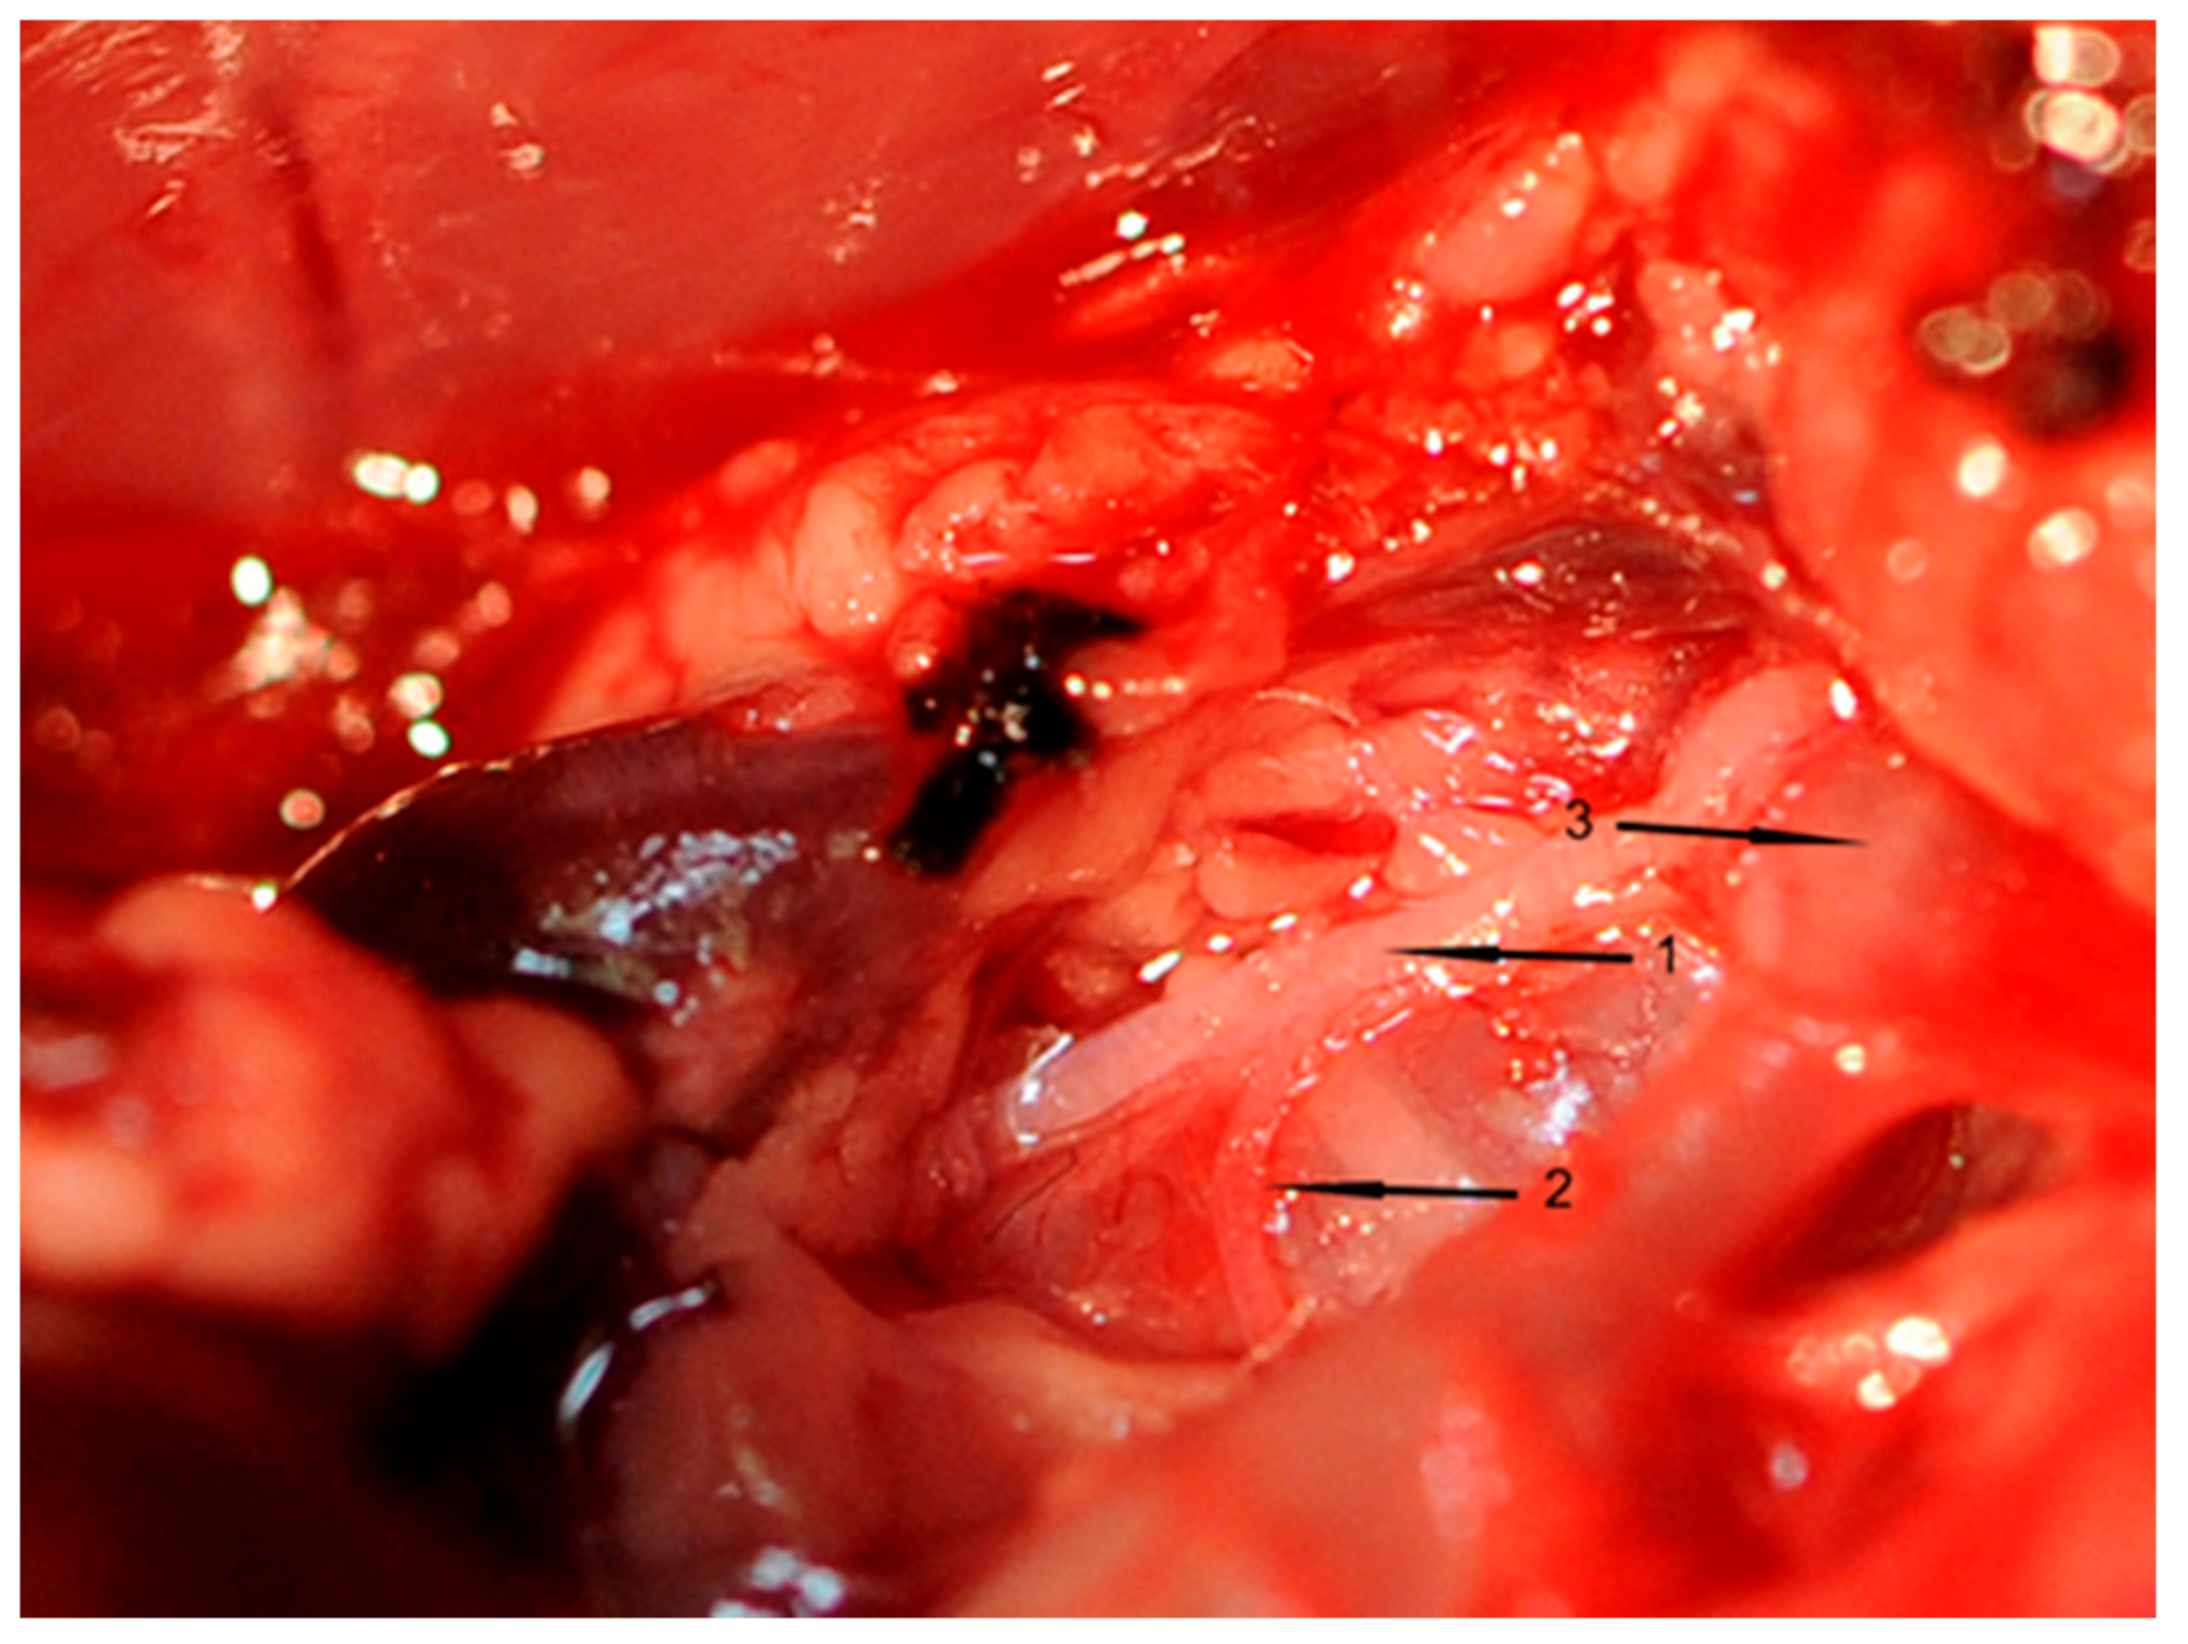

All inserted catheters were fixed (6.0 nylon threads) accurately before the rat’s chest was opened. A 3-cm incision was made to divide the skin and muscle layers. An electrocautery device (Aesculap, Tuttlingen, Germany) was used to avoid or stop bleeding from intercostal arteries. The thorax was opened between the first rib to above the diaphragm using scissors. To prepare, loop, and cut the right cardiac vagus nerve (VGX), a small part of the right thymus was resected. Thereafter, the right cardiac nerve branch of each rat was exposed (Figure 7), which was cut in rats of groups II and IV. This surgical procedure took one hour in total.

Figure 7.

Representative figure of right cardiac vagus nerve preparation. 1 = Nervus vagus dexter, 2 = Cardiac branch of the right vagus nerve, 3 = Truncus brachiocephalicus.